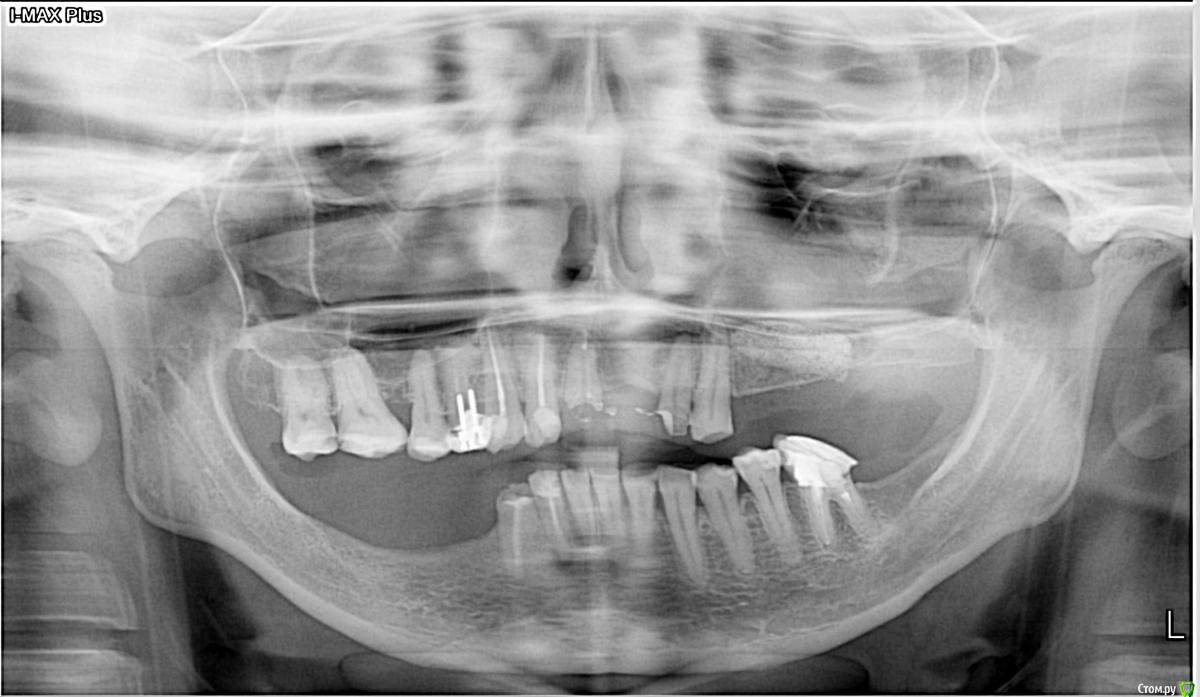

dantist_movani Опубликовано 8 октября, 2015 Поделиться Опубликовано 8 октября, 2015 Мой первый яйце лифтинг) 6 Ссылка на комментарий

kamranchick Опубликовано 22 октября, 2016 Поделиться Опубликовано 22 октября, 2016 Сегодня сделал первый в жизни открытый синус 2 часа ушло на все про все) 1 Ссылка на комментарий

АнтонТЛТ Опубликовано 22 октября, 2016 Поделиться Опубликовано 22 октября, 2016 Камран, мало поднял 1 Ссылка на комментарий

kamranchick Опубликовано 22 октября, 2016 Поделиться Опубликовано 22 октября, 2016 Камран, мало поднялБоялся если честно, и до какого уровня надо было поднимать....Проблема в том, что как от небной стенки отслаивать пазуху? Ссылка на комментарий